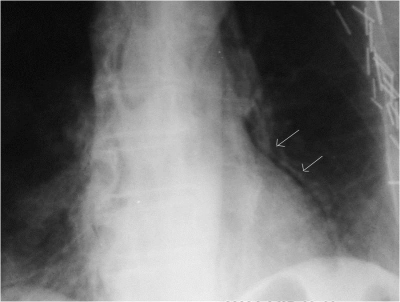

- צילום חזה: בצילום ניתן לראות סימנים של הרחבת המיצר, חזה אוויר, אוויר במיצר (פנאומומדיאסטינום) (תצלום 9.1), תפליט פלאורלי ותמט ריאתי. ב-9% מהחולים צילום החזה תקין.

- צילום ושט: לאחר בליעת בריום. במתן חומרי ניגוד, כגון Lipiodol או Gastrografin, קשה לעתים להדגים את מקום הנקב, ואז יש להשתמש בבריום. ב-90% מהחולים תודגם ההתנקבות (תצלום 10.1).

- אישור לאבחנה נעשה בכל מקרה על-ידי צילום ושט לאחר בליעת חומר ניגוד (תצלום 9.1 ).